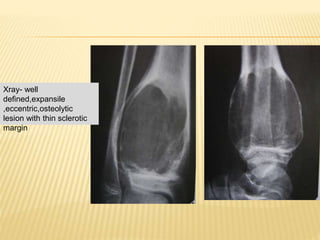

ANEURYSMAL BONE CYST

 expansile, blood filled cystic cavity separated

by connective tissue{not lined by

endothelium}

 <20 yr age

Xray- well

defined,expansile

,eccentric,osteolytic

lesion with thin sclerotic

margin